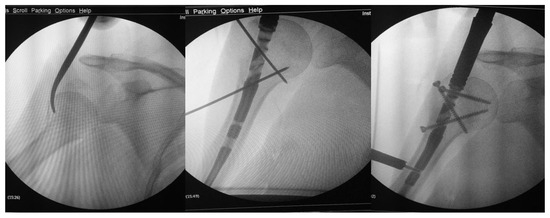

A Modified Technique for Medial Pin Placement in Pediatric Supracondylar Humerus Fractures

by Zhi-Kang Yao, Li-Kai Kuo and Wei-Ning Chang

Surg. Tech. Dev. 2025, 14(4), 36; https://doi.org/10.3390/std14040036 - 21 Oct 2025

Background: Displaced pediatric supracondylar humerus fractures (PSHFs) commonly require surgical treatment. Medial pin placement can cause iatrogenic ulnar nerve injury. This study presents a modified, step-by-step cross-pinning technique for PSHFs designed to avoid iatrogenic ulnar nerve injury. Methods: We retrospectively included [...] Read more.

Background: Displaced pediatric supracondylar humerus fractures (PSHFs) commonly require surgical treatment. Medial pin placement can cause iatrogenic ulnar nerve injury. This study presents a modified, step-by-step cross-pinning technique for PSHFs designed to avoid iatrogenic ulnar nerve injury. Methods: We retrospectively included patients with PSHF (Gartland types III or IV) who underwent closed reduction and percutaneous cross-pinning at our hospital from June 2014 to December 2024. Demographic data, fracture type, and preoperative and postoperative neurological deficits were recorded. Results: A total of 40 patients (16 boys and 24 girls) with a mean age of 6.6 ± 2.2 years (range, 2–14) were included. Most injuries were type III (35/40; 87.5%), whereas five patients (12.5%) had type IV injuries. Our technique resulted in no new cases of postoperative ulnar neuropathy. Conclusions: This study describes a modified medial pin insertion technique for unstable PSHFs. Careful attention to medial pin placement can minimize iatrogenic ulnar nerve injury. Full article